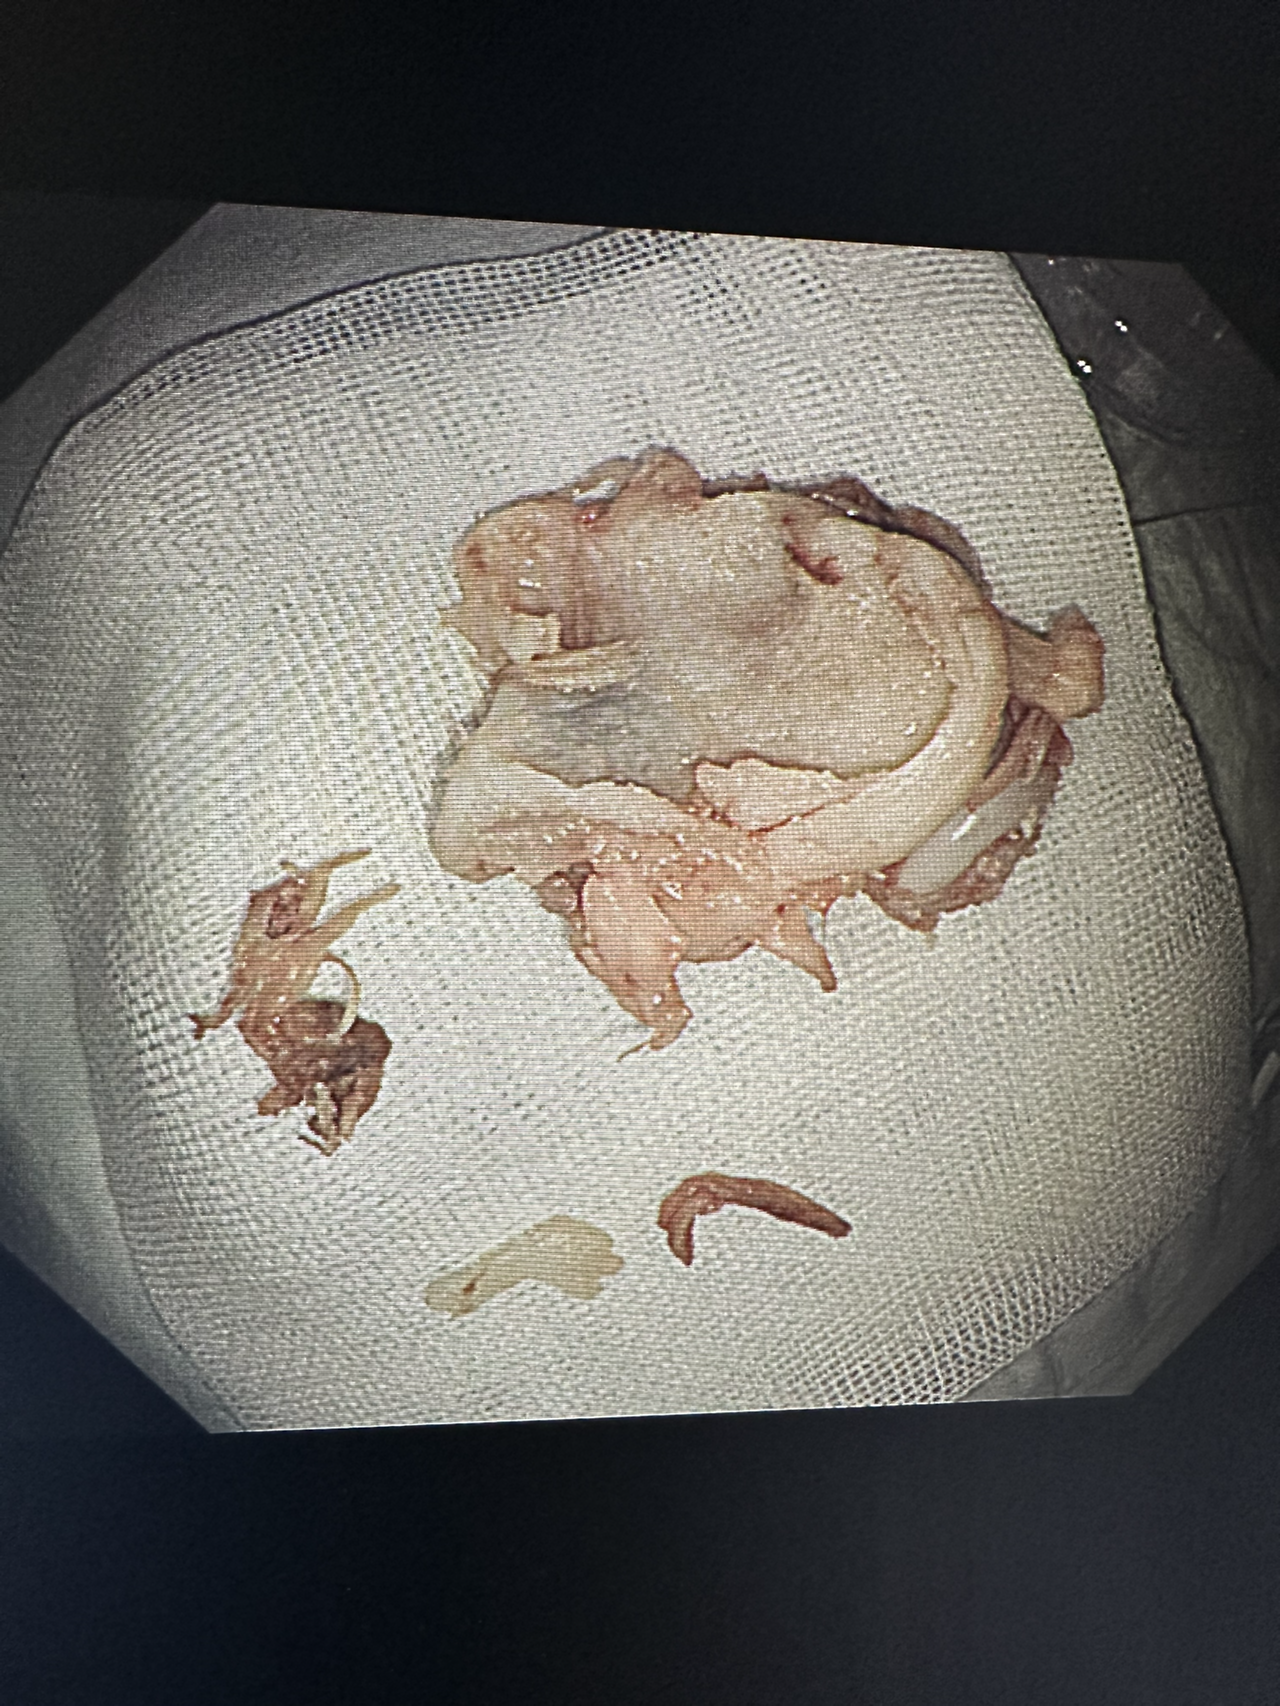

몇 개월 동안 뺐던 생선 가시들이다. 얼핏 보면 커 보이지 않지만 pyriforn sinus(이상와)의 크기보다 큰 이물들은 나오면서도 상처가 생길 수 있고 식도에도 상처를 입힌다. 몇 년 전, 생선 가시가 식도에 박혀있는 환자가 종합병원에서 내시경을 하고 응급실로 왔었다. CT상엔 동맥에 1/3이 침범해 있었고 가시가 박혀 있는 주변부는 농이 나오고 있었다. 다음날 수술실에서 흉부외과와 조인해서 내시경을 했다. 우리가 내시경으로 가이드를 하고 가시를 제거하면 출혈을 잡지 못할 것이기에 개흉수술을 바로 진행할 예정이었다. 다행히 출혈은 심하지 않았고 내시경적으로 해결할 수 있었지만 그 아찔함이란. 그만큼 생선가시를 삼키면 위험하다. 김치나 밥을 삼켜 빼는 것보단 내시경적으로 제거하는 것이 바람직하다.

술을 먹고 실수로 삼키고, 약을 껍질채 삼키기도 한다. 이어폰을 삼키고 사탕 막대와 집게도 삼킨다. 기도가 아닌 식도로 들어가서 망정이지 틀니나 치아는 조심해야 한다. 이렇게나 대한민국 국민들은 다채롭게 삼키는구나.